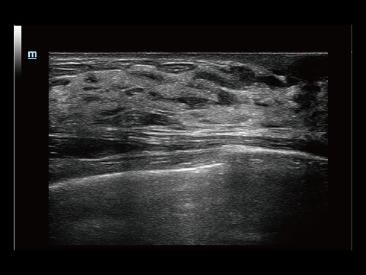

Desde que a empresa foi fundada, a Mindray est├Ī continuamente explorando novas maneiras de melhorar a confian?a no diagn├│stico. Alimentada pela mais revolucion├Īria tecnologia ZONE Sonography?, a nova plataforma Resona 7's ZST+ traz uma qualidade de imagem ultra-som a um n├Łvel superior por aquisi??o de zona e processamento de dados do canal.

Assim como o n├Łvel de qualidade de imagem premium, o Resona 7 tamb├®m melhora as capacidades de investiga??o cl├Łnica com o revolucion├Īrio Fluxo V para avalia??o hemodin?mica vascular e a aquisi??o de plano mais inteligente do conjunto de dados 3D para diagn├│stico CNS fetal. Combinando a opera??o mais intuitiva baseada em gesto de multi-toques e todos os recursos cl├Łnicos essenciais, Resona 7 est├Ī realmente conduzindo novas ondas na inova??o de ultra-som.